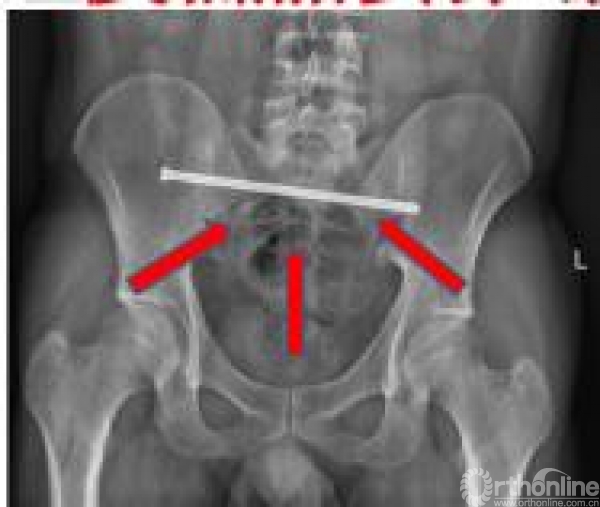

患者5 随访(骨盆LC-2损伤+髋臼):经皮LC-2螺钉+前柱螺钉